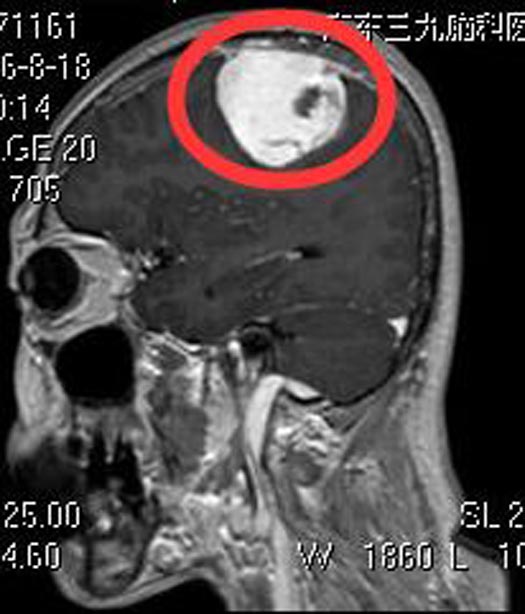

林阿姨四天前突发头痛,伴有肢乏力,呕吐,当地医院头颅CT检查显示:左侧顶部高密度病灶,考虑为脑梗塞后出血,予对症处理。症状无好转。

转入广东三九脑科医院综合神经外科,进一步行头颅MR检查结果:左侧顶部占位病变,范围约61.6mm×41mm×45.5mm;头颅CTA检查提示:左侧顶部占位病灶(含出血,肿瘤卒中可能性大)。结合CTA检查其内肿瘤供血血管丰富,周围包绕供血动脉,脑膜动脉来源可能性大,首先考虑脑膜瘤或血管外皮瘤可能。

由于肿瘤血供丰富,为保障手术质量,术前予肿瘤部分供血血管栓塞,后由鲁明主任主刀,在全麻下行左额顶脑膜瘤切除术。导航定位肿瘤位置,术中见肿瘤呈烂鱼肉状,质软,有陈旧性出血,边界较清,显微镜下顺利全切肿瘤。术后病理结果提示:微囊型脑膜瘤 WHO I级。

▲术前